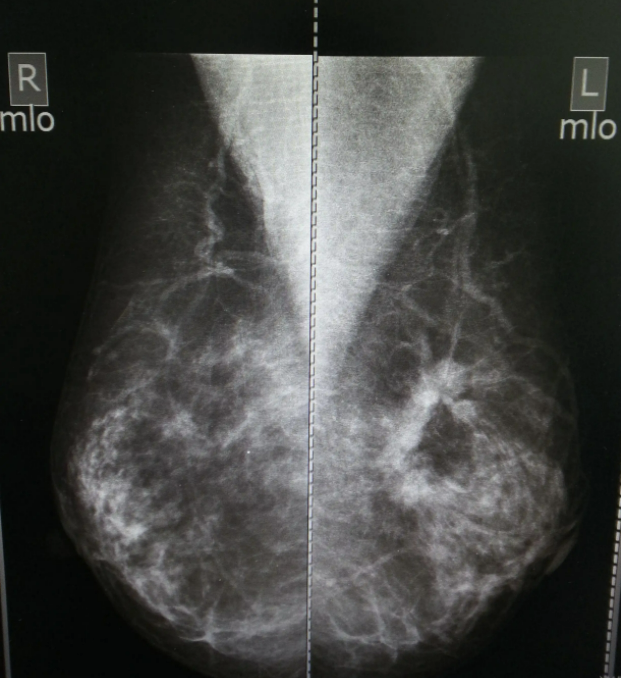

鉬靶照相是利用軟X線對乳腺組織進行攝像,通俗地說,就是乳腺的“夾板拍片”,是將乳腺放置于兩塊特制平板中,壓緊后進行攝片,以達到對乳腺內(nèi)組織進行診斷的目的。

依據(jù)病變與正常乳腺組織間的密度差,鉬靶攝影下乳腺癌的表現(xiàn)為腫塊結(jié)節(jié)影和鈣化灶。細沙樣、蠕蟲形、成簇形的鈣化影也是早期乳腺癌特征性的表現(xiàn),這樣的檢查有利于早期發(fā)現(xiàn)乳腺癌。

02 鉬靶影像中,乳腺癌是什么樣子?

乳腺癌腫瘤生長較快,內(nèi)部常出現(xiàn)壞死、鈣化,這些癥狀容易被鉬靶檢測到。

乳腺癌的鈣化經(jīng)常表現(xiàn)為細小泥沙樣鈣化,這種鈣化很密集,呈一簇一簇的,粗細不均,濃淡不一。鈣化可能在腫塊內(nèi),也可能在腫塊外,也可能看不到腫塊,只看到鈣化。

部分惡性腫瘤,鉬靶影像僅表現(xiàn)為單純腫塊,典型的乳腺癌表現(xiàn)為圓形或類圓形,可能有分葉狀、毛刺狀或觸角狀。